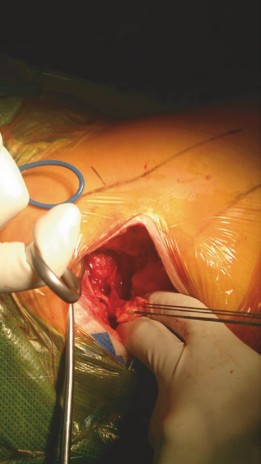

Femoral Elevation and Preparation

This is the most critical and challenging phase of the off-table DAA. Without a traction table to pull the femur distally and externally rotate it, the surgeon must mobilize the proximal femur into the surgical window manually.

The operative leg is manipulated into a "figure-of-four" position: the hip is extended, maximally externally rotated, and adducted. The foot is often placed in the sterile pouch on the side of the table, or the leg is crossed beneath the contralateral leg.

To allow the proximal femur to elevate anteriorly, sequential capsular releases are mandatory. The sequence typically involves:

1. Superior Release: Releasing the superior capsule from the base of the greater trochanter ("saddle" release).

2. Posterior Capsular Release: Releasing the remaining posterior capsule along the intertrochanteric crest. This must be done carefully to avoid injury to the short external rotators.

3. Pubofemoral Release: Releasing the medial/inferior capsule.

A specialized retractor (e.g., a dual-pronged femoral elevator) is placed posterior to the greater trochanter to lever the femur anteriorly and laterally. A medial retractor protects the calcar.